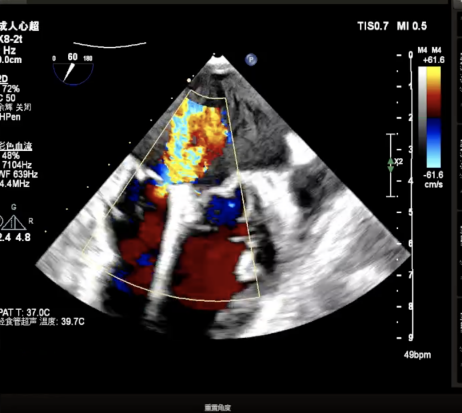

X-plane视窗可见二尖瓣病变区脱垂,重度偏心性返流.

3D enface view示二尖瓣P2P3区瓣叶脱垂,偏心性返流